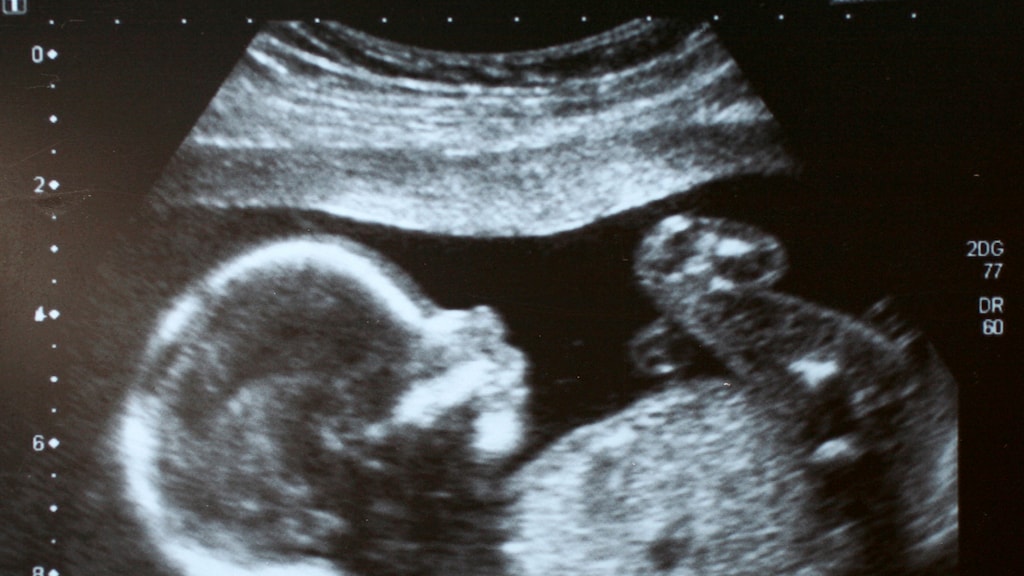

Om beter te kunnen bepalen of een hoogzwangere vrouw moet worden ingeleid als ze de baby wat minder voelt, biedt een extra echometing uitkomst. Die betere inschatting zorgt uiteindelijk voor minder complicaties bij de baby. Dat meldt het Universitair Medisch Centrum Groningen (UMCG).